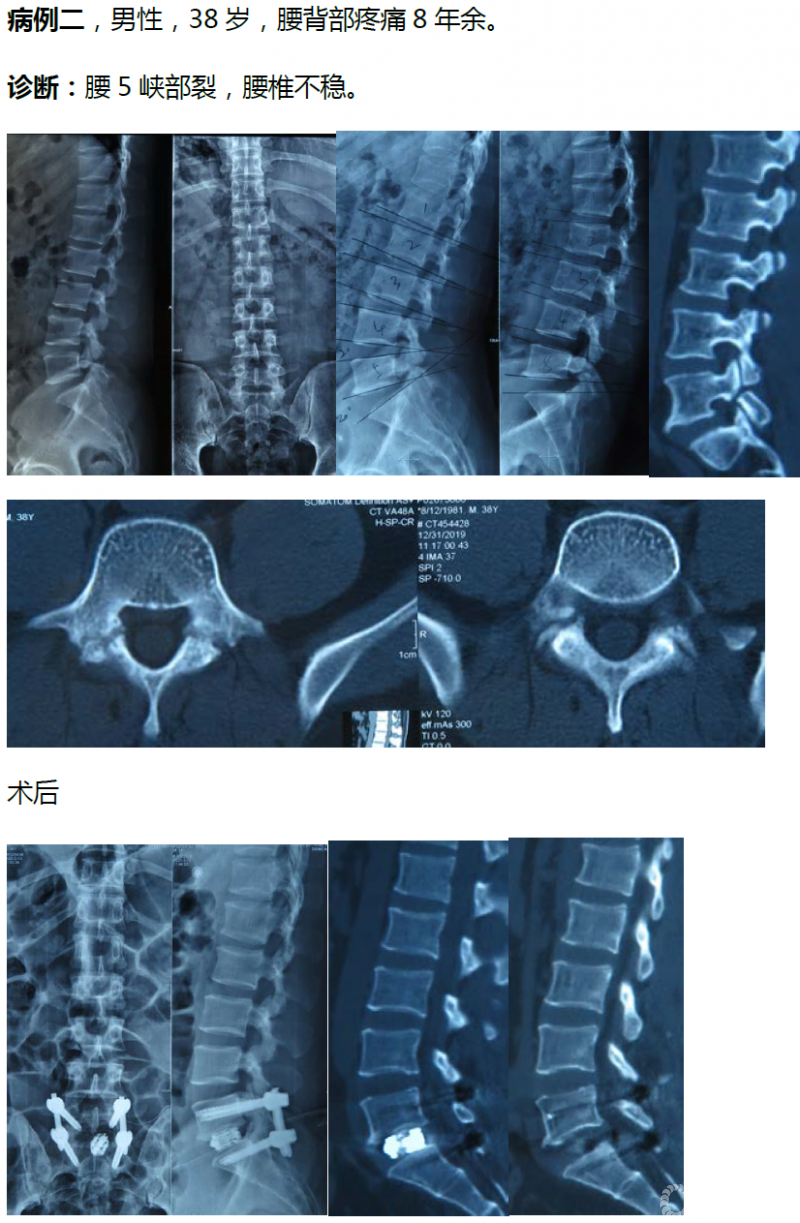

病例分享:(滑动查看)